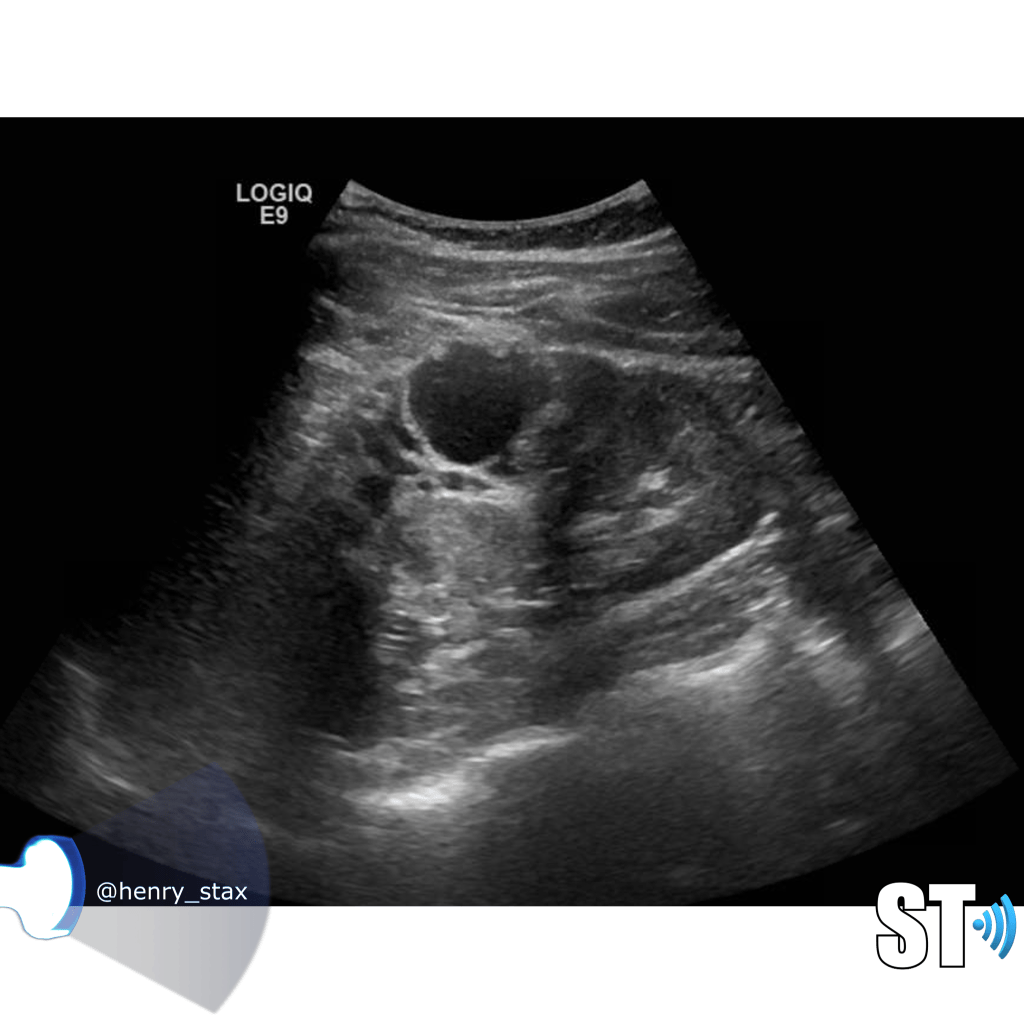

ADPKD

In Autosomal Dominant Polycystic Kidney Disease (ADPKD) the kidneys are normal at birth with cysts developing overtime. By age 30 years, approximately 68% of patients will have visible cysts by ultrasound. Eventually, virtually all patients develop cysts. The disease is transmitted in an autosomal dominant pattern, meaning you only one abnormal gene from one parent.

One abnormal gene from one parent

- Adult

- 4-10% of all cases of ESRF

- Kidneys appear normal early on

- Liver, pancreas and spleen cysts